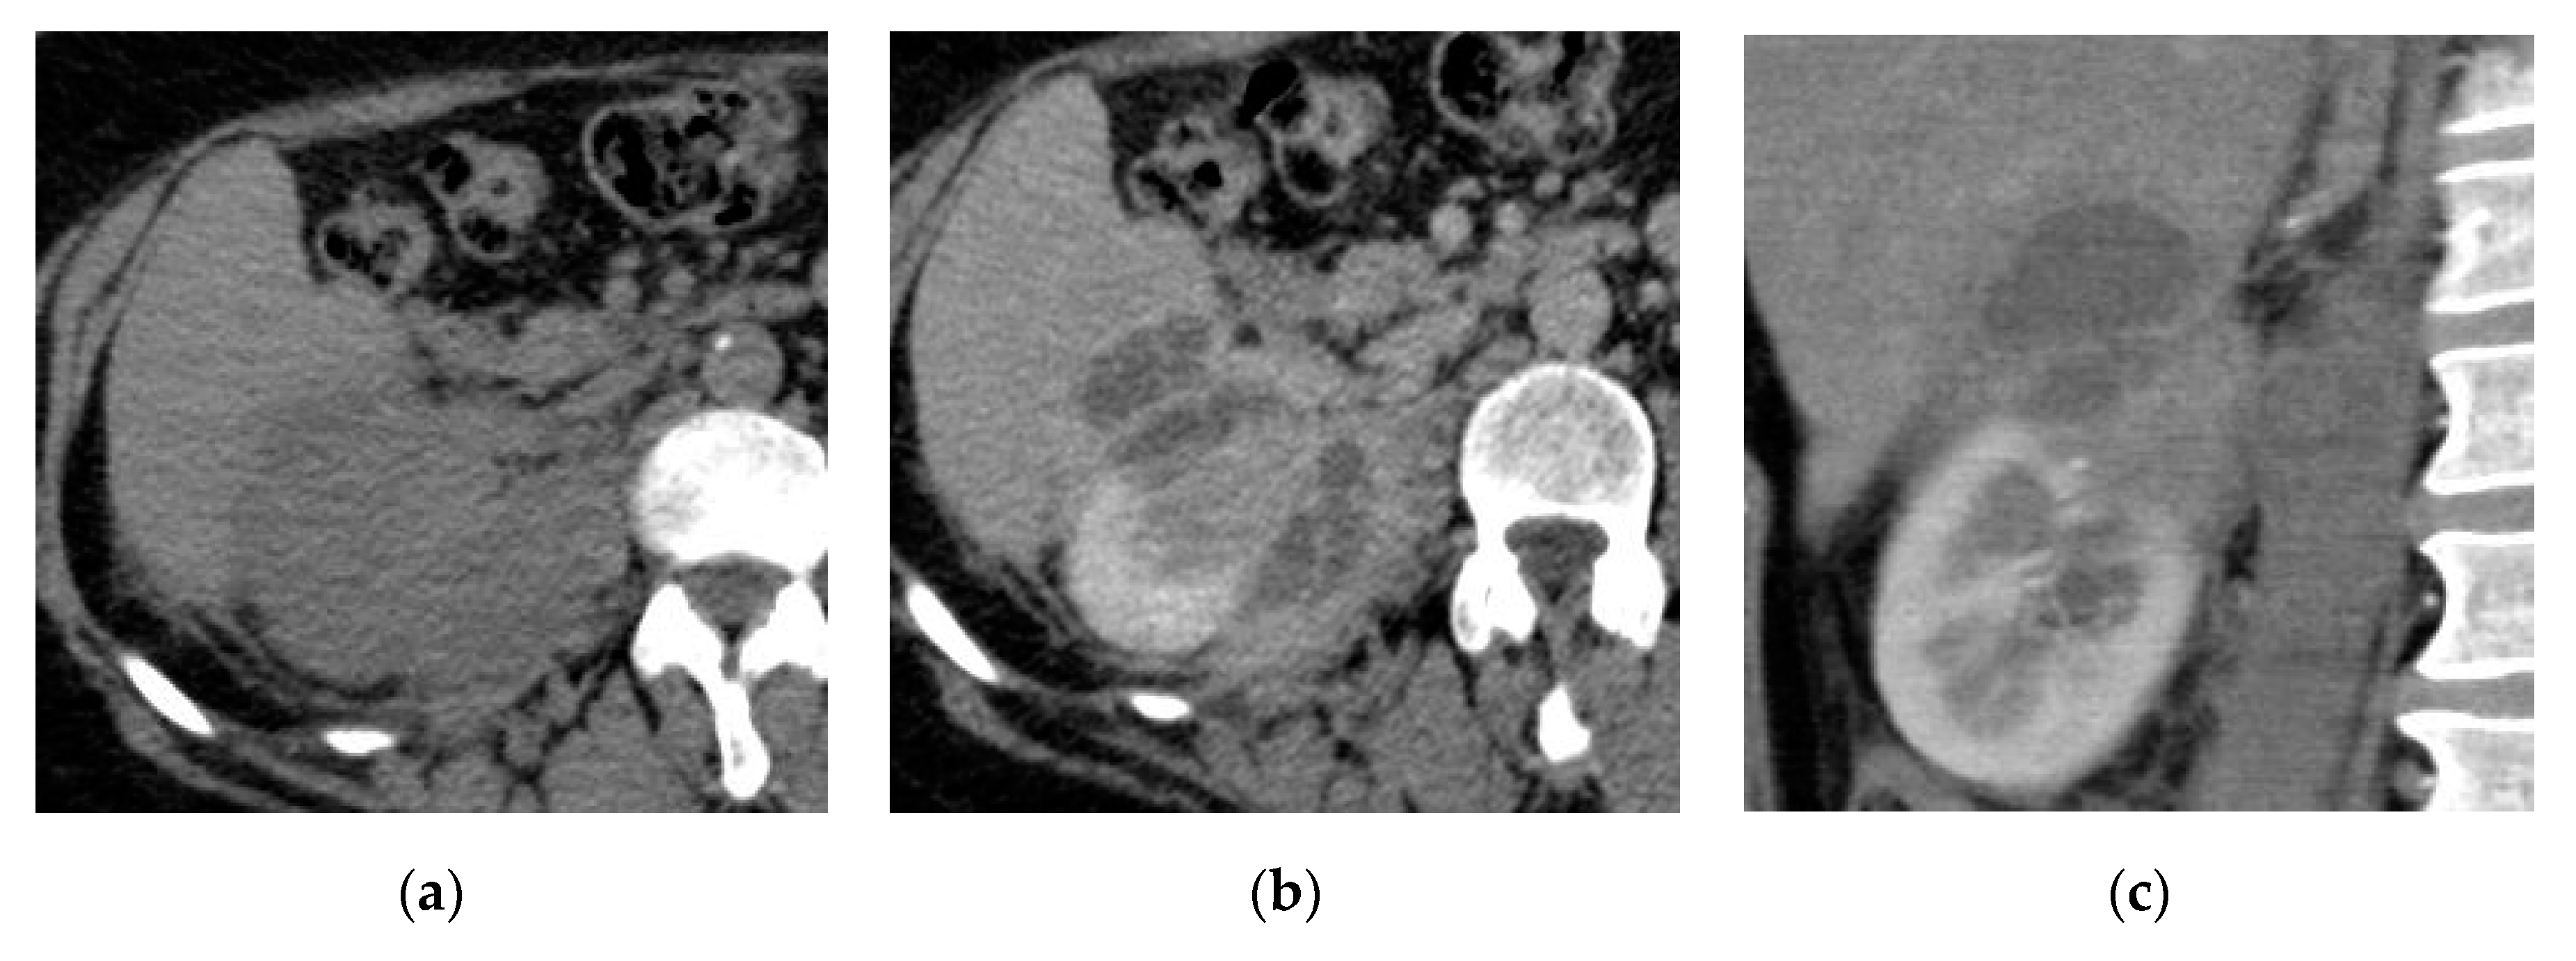

2.3. Pyonephrosis

| Pyonephrosis | Dilated thick-walled hyperenhancing collecting system, distended with high attenuation pus-filled fluid, fluid—fluid layering at T2WI, and thinning of the renal cortex. |